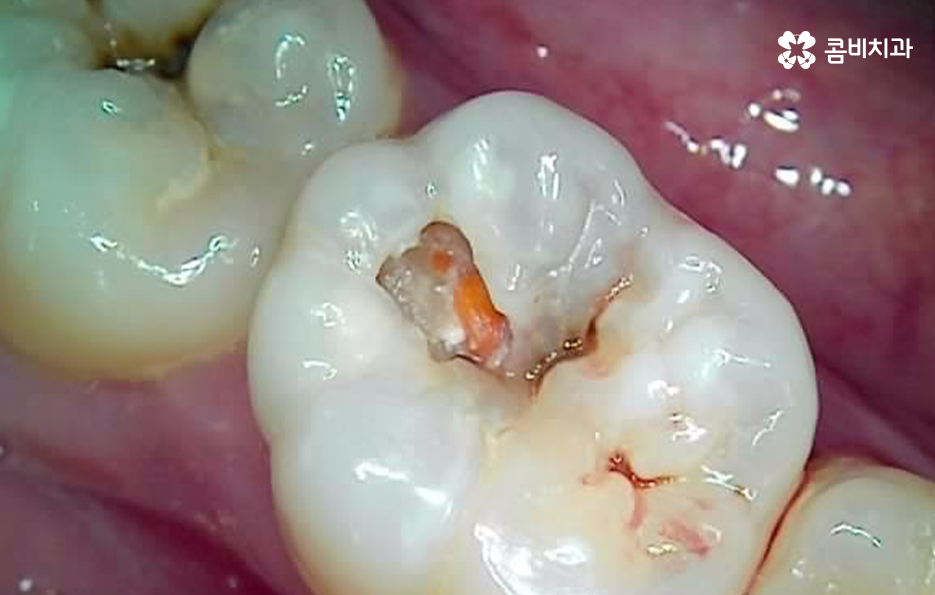

우선 충치가 신경조직까지 진행된 경우를 먼저 살펴보면 신경에 도달한 충치는 보통 극심한 시림과 통증을 느끼게 할 거예요. 충치의 단계로 비교하자면 법랑질에 발생한 충치의 경우 별다른 증상을 못 느끼는 경우가 대부분인 반면에 신경에 충치가 도달하면 시림이나 통증이 매우 크다고 느낄 정도이며 심한 경우 일상생활이 어렵고 잠을 자기 어려울 정도로 불편함도 느낄 거예요. 그리고 간혹 선천적으로 신경이 뾰족한 경우가 있는데, 이 경우 신경이 노출되지 않아도 차가운 물을 먹을 때 시리거나 저작 시 통증이 발생할 수 있는데, 이 경우에도 신경치료 필요하고, 방치할 경우 신경이 변형되거나 죽으면서 뿌리 쪽에 염증이 생기는 경우가 있어요.

이처럼 충치로 인해 신경치료가 필요한 경우에는 참지 마시고 치료를 빠르게 받는 것이 일상생활과 건강을 위해서도 필요하며 자연치아의 보존에 있어서도 권장하고 있어요